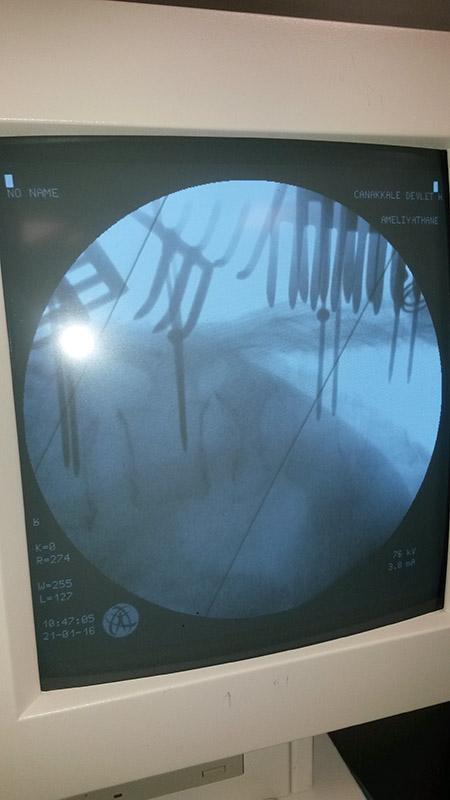

REBORN SPINAL STABILIZATION SYSTEM

Spinal Stabilization System Reborn ® Spinal Fixation System is an implant system used to treat a r...